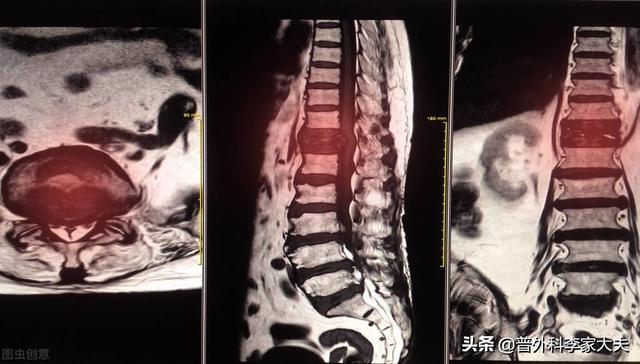

Imagerie par résonance magnétique des métastases osseuses

Montrant un cancer avec métastases osseuses survenant dans la colonne vertébrale thoracique